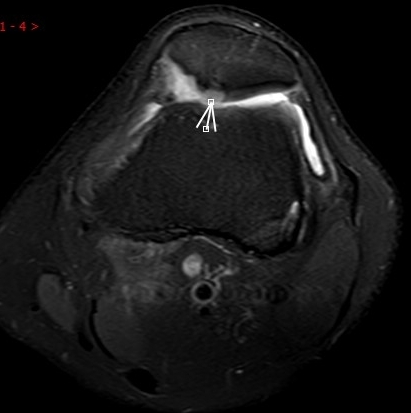

1. “咯吱響”+“卡頓感”——半月板的“碎玻璃警報(bào)”

場(chǎng)景:下蹲時(shí)膝蓋“咯噔”彈響,起身像被“卡住”

MRI偵查:精準(zhǔn)捕捉半月板撕裂或變性(半月板內(nèi)高信號(hào)),避免拖成“關(guān)節(jié)交鎖”

(半月板撕裂)